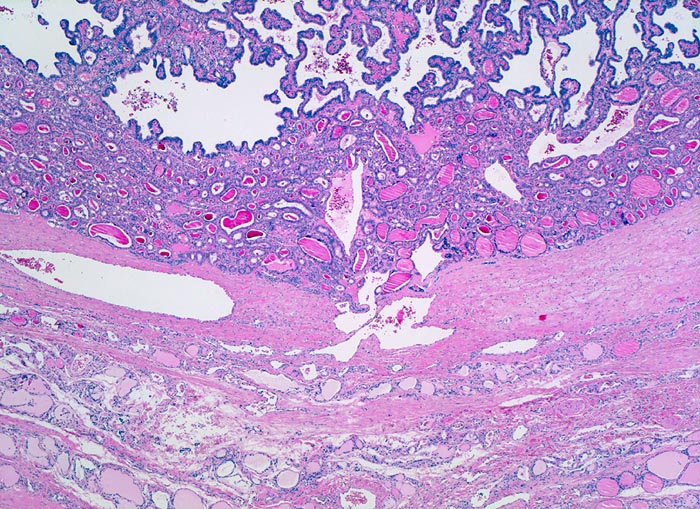

PathoPic ID 4735 - papilläres Schilddrüsenkarzinom

papilläres Schilddrüsenkarzinom

maligner Tumor

Schilddrüse

Endokrinium

Bindegewebige

Kapsel zwischen Karzinom und

atrophem Parenchym. Das Karzinom bildet

Follikel und

papilläre Strukturen.

In der Feinnadelpunktion eines 2cm grossen kalten Knotens werden Karzinomzellen nachgewiesen vereinbar mit einem papillären Schilddrüsenkarzinom.

Nur etwa 10% der papillären Karzinome sind vollständig bekapselt. Die bekapselten Tumoren haben eine bessere Prognose.

Histologie

25

46